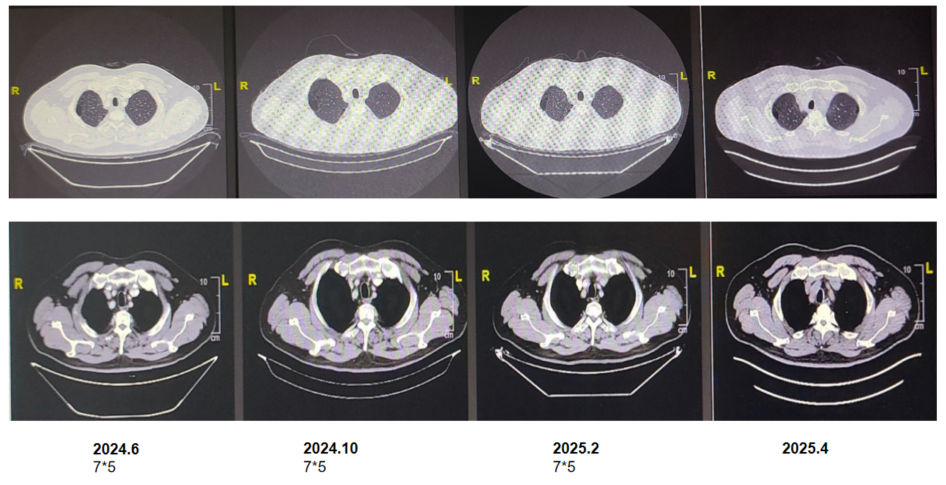

胸部CT+PET/CT(2023年5月17日):右肺尖叶占位,范围约4.4*4.1cm,FDG高代谢,恶性肿瘤可能大;伴周围炎;全身多发骨转移,右侧淋巴结转移,纵隔、腹膜后、两侧髂血管旁、左侧臀肌间隙淋巴结转移可能。鼻咽部炎症可能;左上肺少许纤维灶;两上肺肺气肿;食管下段炎症可能;肝囊肿。

图片1.png

图1. 胸部CT+PET/CT基线(2023年5月17日)

PET/CT(2023年5月17日):骨盆多处骨质破坏,右侧髂骨为甚(骨病灶尺寸:6 cm* 4.5cm),周围伴软组织肿块,放射性浓聚。此外,骨骼多处放射性摄取增高。ECT示全身多发骨转移,左侧前肋(约第一肋骨)、腰椎、右侧骶髂关节、右侧耻骨、左侧髋关节为著。

图片9.png

图2. 原发灶与骨转移灶对比

(骨转移灶图左,中为PET/CT,右为骨转移病灶示意图)